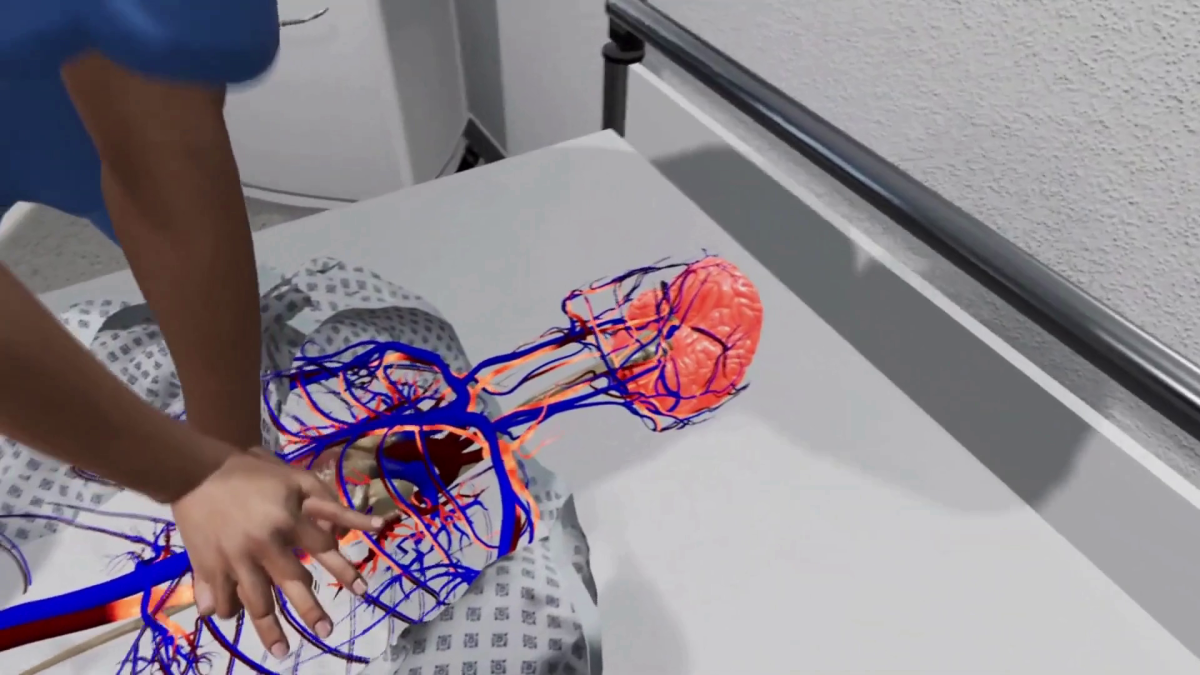

- 3D Dental Animation for procedures like cleaning, cavity filling, root canals, etc.

- Detailed oral health explainer videos that are engaging and easy to understand

I have extensive experience in dental visualization and animation, ensuring that every project is accurate, professional, and visually appealing. I use advanced software to deliver high-quality videos tailored to your specific needs.

Tagged : 3d dental animation, 3d medical animation, dental models for oral health explainer, surgical animation, tray whitening